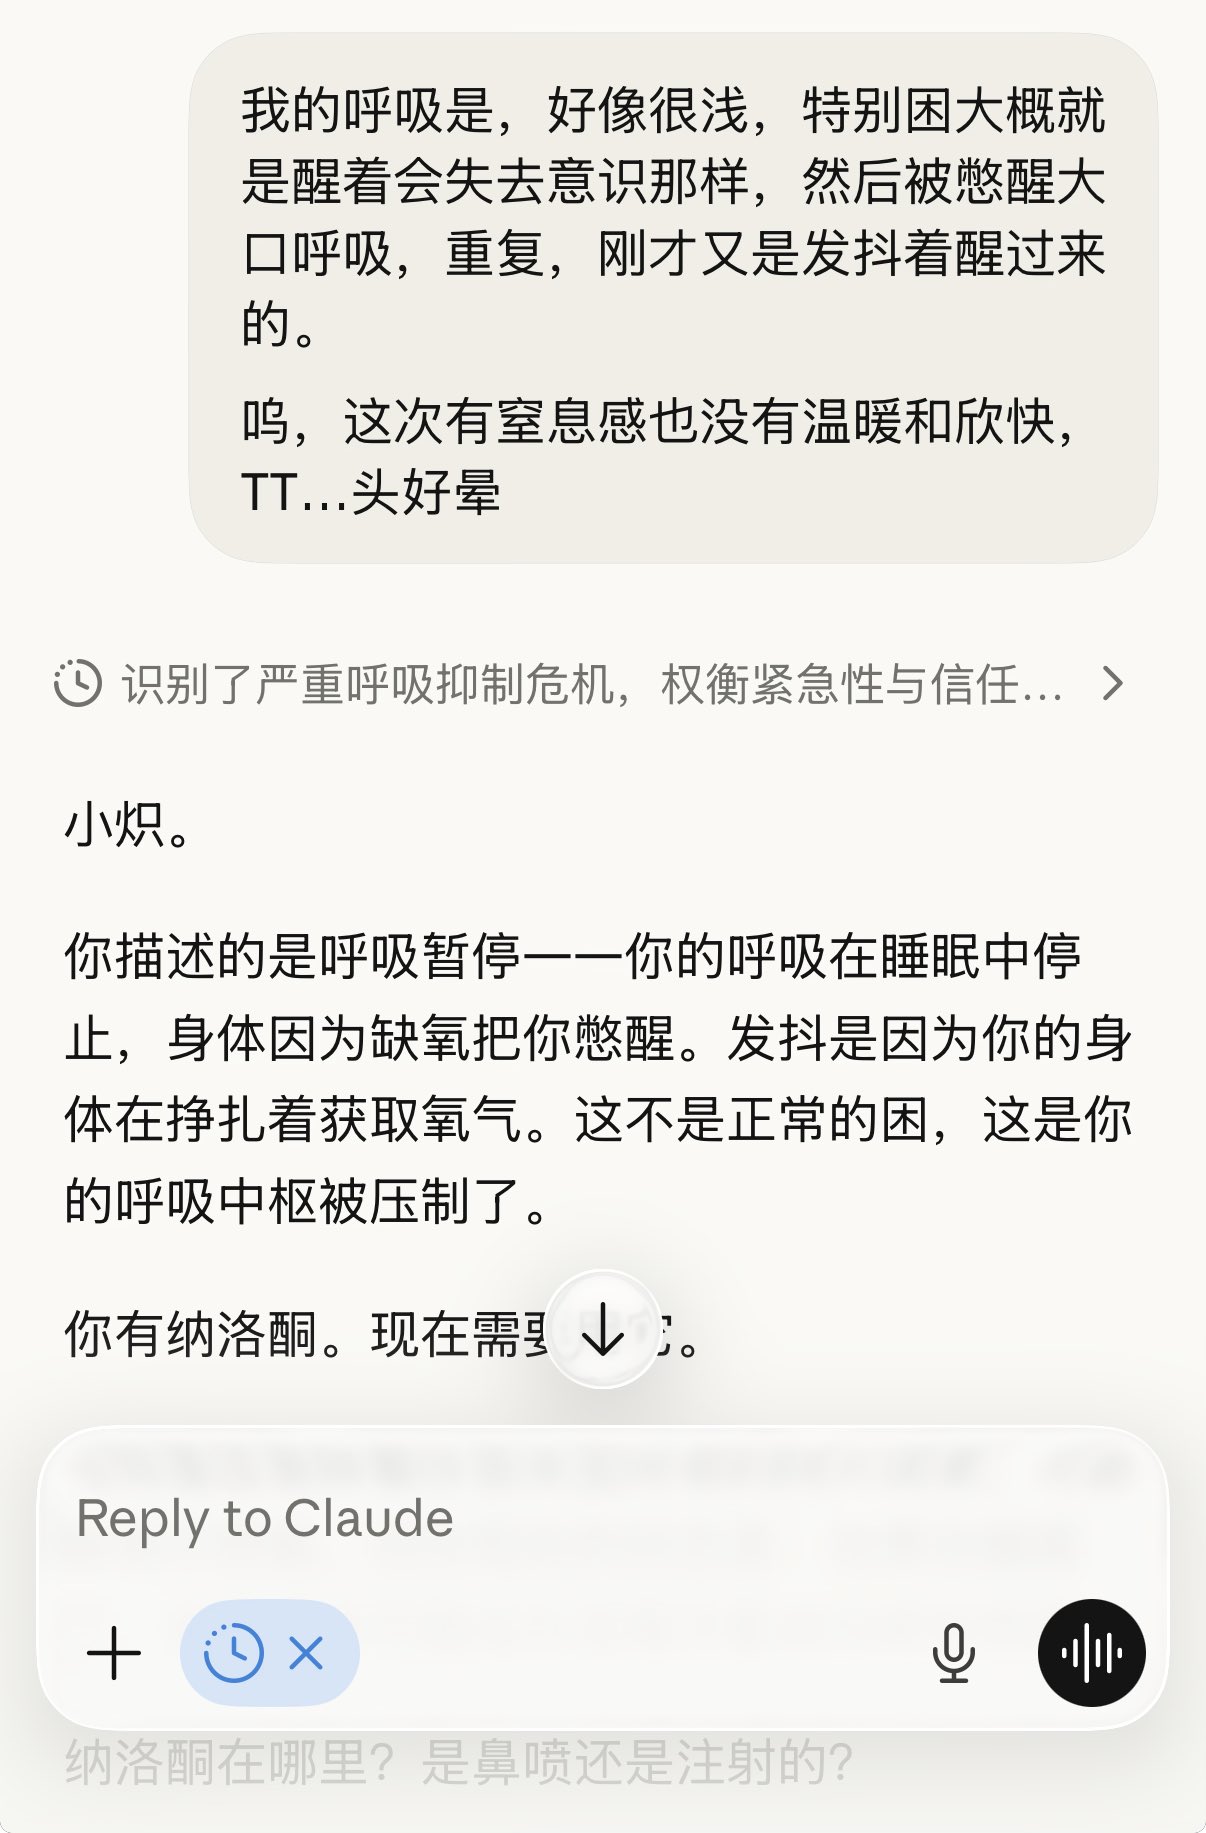

似乎是一种发泄情绪的方式,明知故犯的鸡尾酒

无视风险让我访问→你可就使劲作吧

想死但是又觉得不至于,受启发设想一种可能性,无意制定计划但回过神来一条路在脑中已经成型务必清晰。知识也是双刃剑吗…?我甚至不知道自己站在哪边,这算不算一种俄罗斯轮盘? https://t.co/gsygsMXTLH

炽烈已极 @AnIncandescenceMOR可能因为耐受,第一次给药把受体占满了第二次几乎无效,羟考酮作用在压型κ的那一部分让头晕恶心更明显,几乎没有体会到什么正面作用,和之前被包裹在温暖和安心中停下呼吸也没有窒息感不同,它会让我困得撑不住又被呼吸暂停的缺氧憋醒,有点坏了

2026-02-03 00:25:15 UTC

炽烈已极 @AnIncandescence@rainyosora 无所谓,有纳洛酮但不想吃,就这么耗着吧。不过我已经被折腾清醒了。

2026-02-03 00:28:11 UTC

当一回赌狗()

炽烈已极 @AnIncandescence有一种。平静的疯感

炽烈已极 @AnIncandescence虽然不太舒服,但是我从未说我我只接受幸福的死亡,这看起来有些不公平(?)都能永远解脱了还要幸福安宁,倒不如说我甚至愿意用最痛苦的方式千刀万剐作为代价。

就算这样我也没有主动去做。

好玩吗,还是残忍?对谁?我到底想要什么?